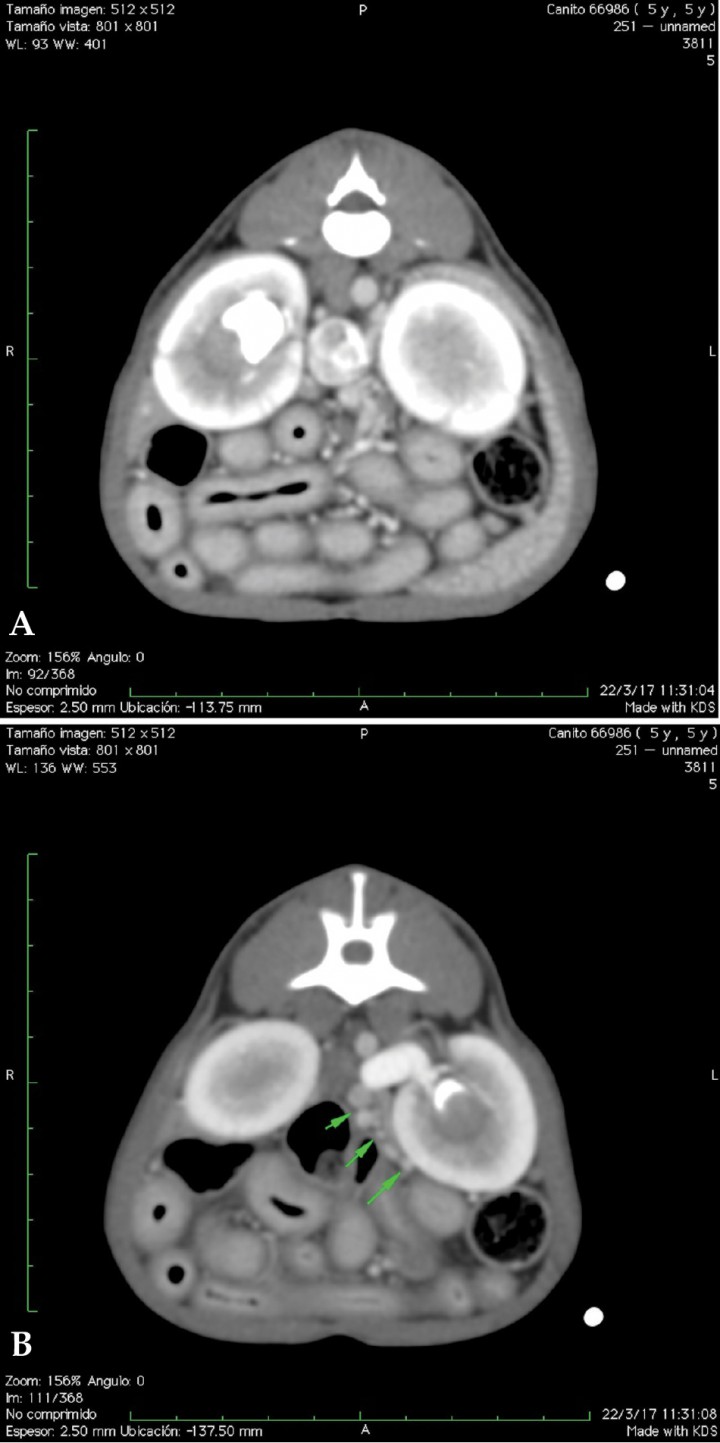

<p>(A) Corte longitudinal, medial al riñón izquierdo. Múltiples vasos sanguíneos distendidos y tortuosos compatibles con shunts portosistémicos extrahepáticos adquiridos. (B) Corte longitudinal, medial al riñón izquierdo. Detalle Doppler color.</p>

Figura 5

(A) Corte longitudinal, medial al riñón izquierdo. Múltiples vasos sanguíneos distendidos y tortuosos compatibles con shunts portosistémicos extrahepáticos adquiridos. (B) Corte longitudinal, medial al riñón izquierdo. Detalle Doppler color.

<p>Imágenes axiales con contraste a nivel renal. (A) Dilatación de la vena cava con múltiples vasos sanguíneos tortuosos adyacentes (shunts portosistémicos adquiridos), urolito en pelvis del riñón derecho. Áreas estriadas hipodensas (captación de contraste irregular) en ambas corticales renales. (B) Dilatación de la vena renal izquierda y pequeños vasos sanguíneos de aspecto tortuosos en la proximidad del riñón izquierdo (shunts portosistémicos adquiridos). Urolito en pelvis del riñón izquierdo. </p>

Figura 9

Imágenes axiales con contraste a nivel renal. (A) Dilatación de la vena cava con múltiples vasos sanguíneos tortuosos adyacentes (shunts portosistémicos adquiridos), urolito en pelvis del riñón derecho. Áreas estriadas hipodensas (captación de contraste irregular) en ambas corticales renales. (B) Dilatación de la vena renal izquierda y pequeños vasos sanguíneos de aspecto tortuosos en la proximidad del riñón izquierdo (shunts portosistémicos adquiridos). Urolito en pelvis del riñón izquierdo.

En perros, las comunicaciones múltiples son comúnmente esplénicas, y se presentan en el área perirrenal izquierda y la raíz del mesenterio (Fig. 5). Esto es debido a que el incremento de la resistencia al flujo sanguíneo portal determina que las conexiones microvasculares no funcionales, presentes al nacimiento entre la vena porta y las vías sistémicas, se tornen funcionales, de manera que las comunicaciones portosistémicas representan dilataciones adquiridas de comunicaciones microvasculares normales entre la vena porta y las venas sistémicas.

En nuestro paciente (Figs. 4, 5 y 7) la presencia de estos shunts múltiples, junto con el perfil de flujo portal y la presencia de ascitis, son altamente sugerentes de que el proceso de base está provocando HTP.